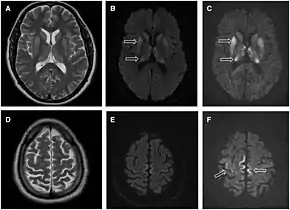

- MRI of the brain – often shows high signal intensity in the caudate nucleus and putamen bilaterally on T2-weighted images.

Imaging of the brain may be performed during medical evaluation, both to rule out other causes and to obtain supportive evidence for diagnosis. Imaging findings are variable in their appearance, and also variable in sensitivity and specificity.[41] While imaging plays a lesser role in diagnosis of CJD,[42] characteristic findings on brain MRI in some cases may precede onset of clinical manifestations.[43]

Brain MRI is the most useful imaging modality for changes related to CJD. Of the MRI sequences, diffuse-weighted imaging sequences are most sensitive. Characteristic findings are as follows:

- Focal or diffuse diffusion-restriction involving the cerebral cortex and/or basal ganglia. In about 24% of cases DWI shows only cortical hyperintensity; in 68%, cortical and subcortical abnormalities; and in 5%, only subcortical anomalies.[44] The most iconic and striking cortical abnormality has been called "cortical ribboning" or "cortical ribbon sign" due to hyperintensities resembling ribbons appearing in the cortex on MRI.[45] The involvement of the thalamus can be found in sCJD, is even stronger and constant in vCJD.[46]

- Varying degree of symmetric T2 hyperintense signal changes in the basal ganglia (i.e., caudate and putamen), and to a lesser extent globus pallidus and occipital cortex.[42]